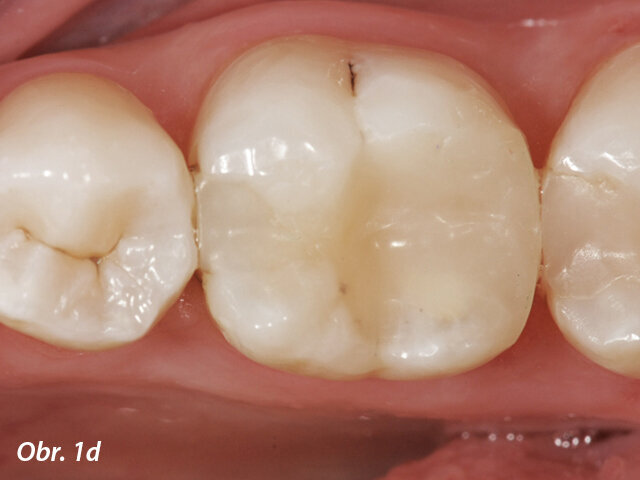

V posledních letech se stala populární terapie zachování vitální pulpy. Běžným materiálem pro překrytí pulpy byl hydroxid vápenatý, ale MTA vykazuje lepší výsledky v biokompatibilitě a úspěšnosti (Aguilar a Linsuwanont 2011). Případy s rozsáhlým kariézním nálezem mohou být úspěšně ošetřeny částečnou pulpotomií a překrytím MTA, což zachová pulpu vitální (obr. 1a–e).

Aplikace MTA s MAP systémem a PD MTA White

Postoperační RTG zobrazující překrytí pulpy s MTA